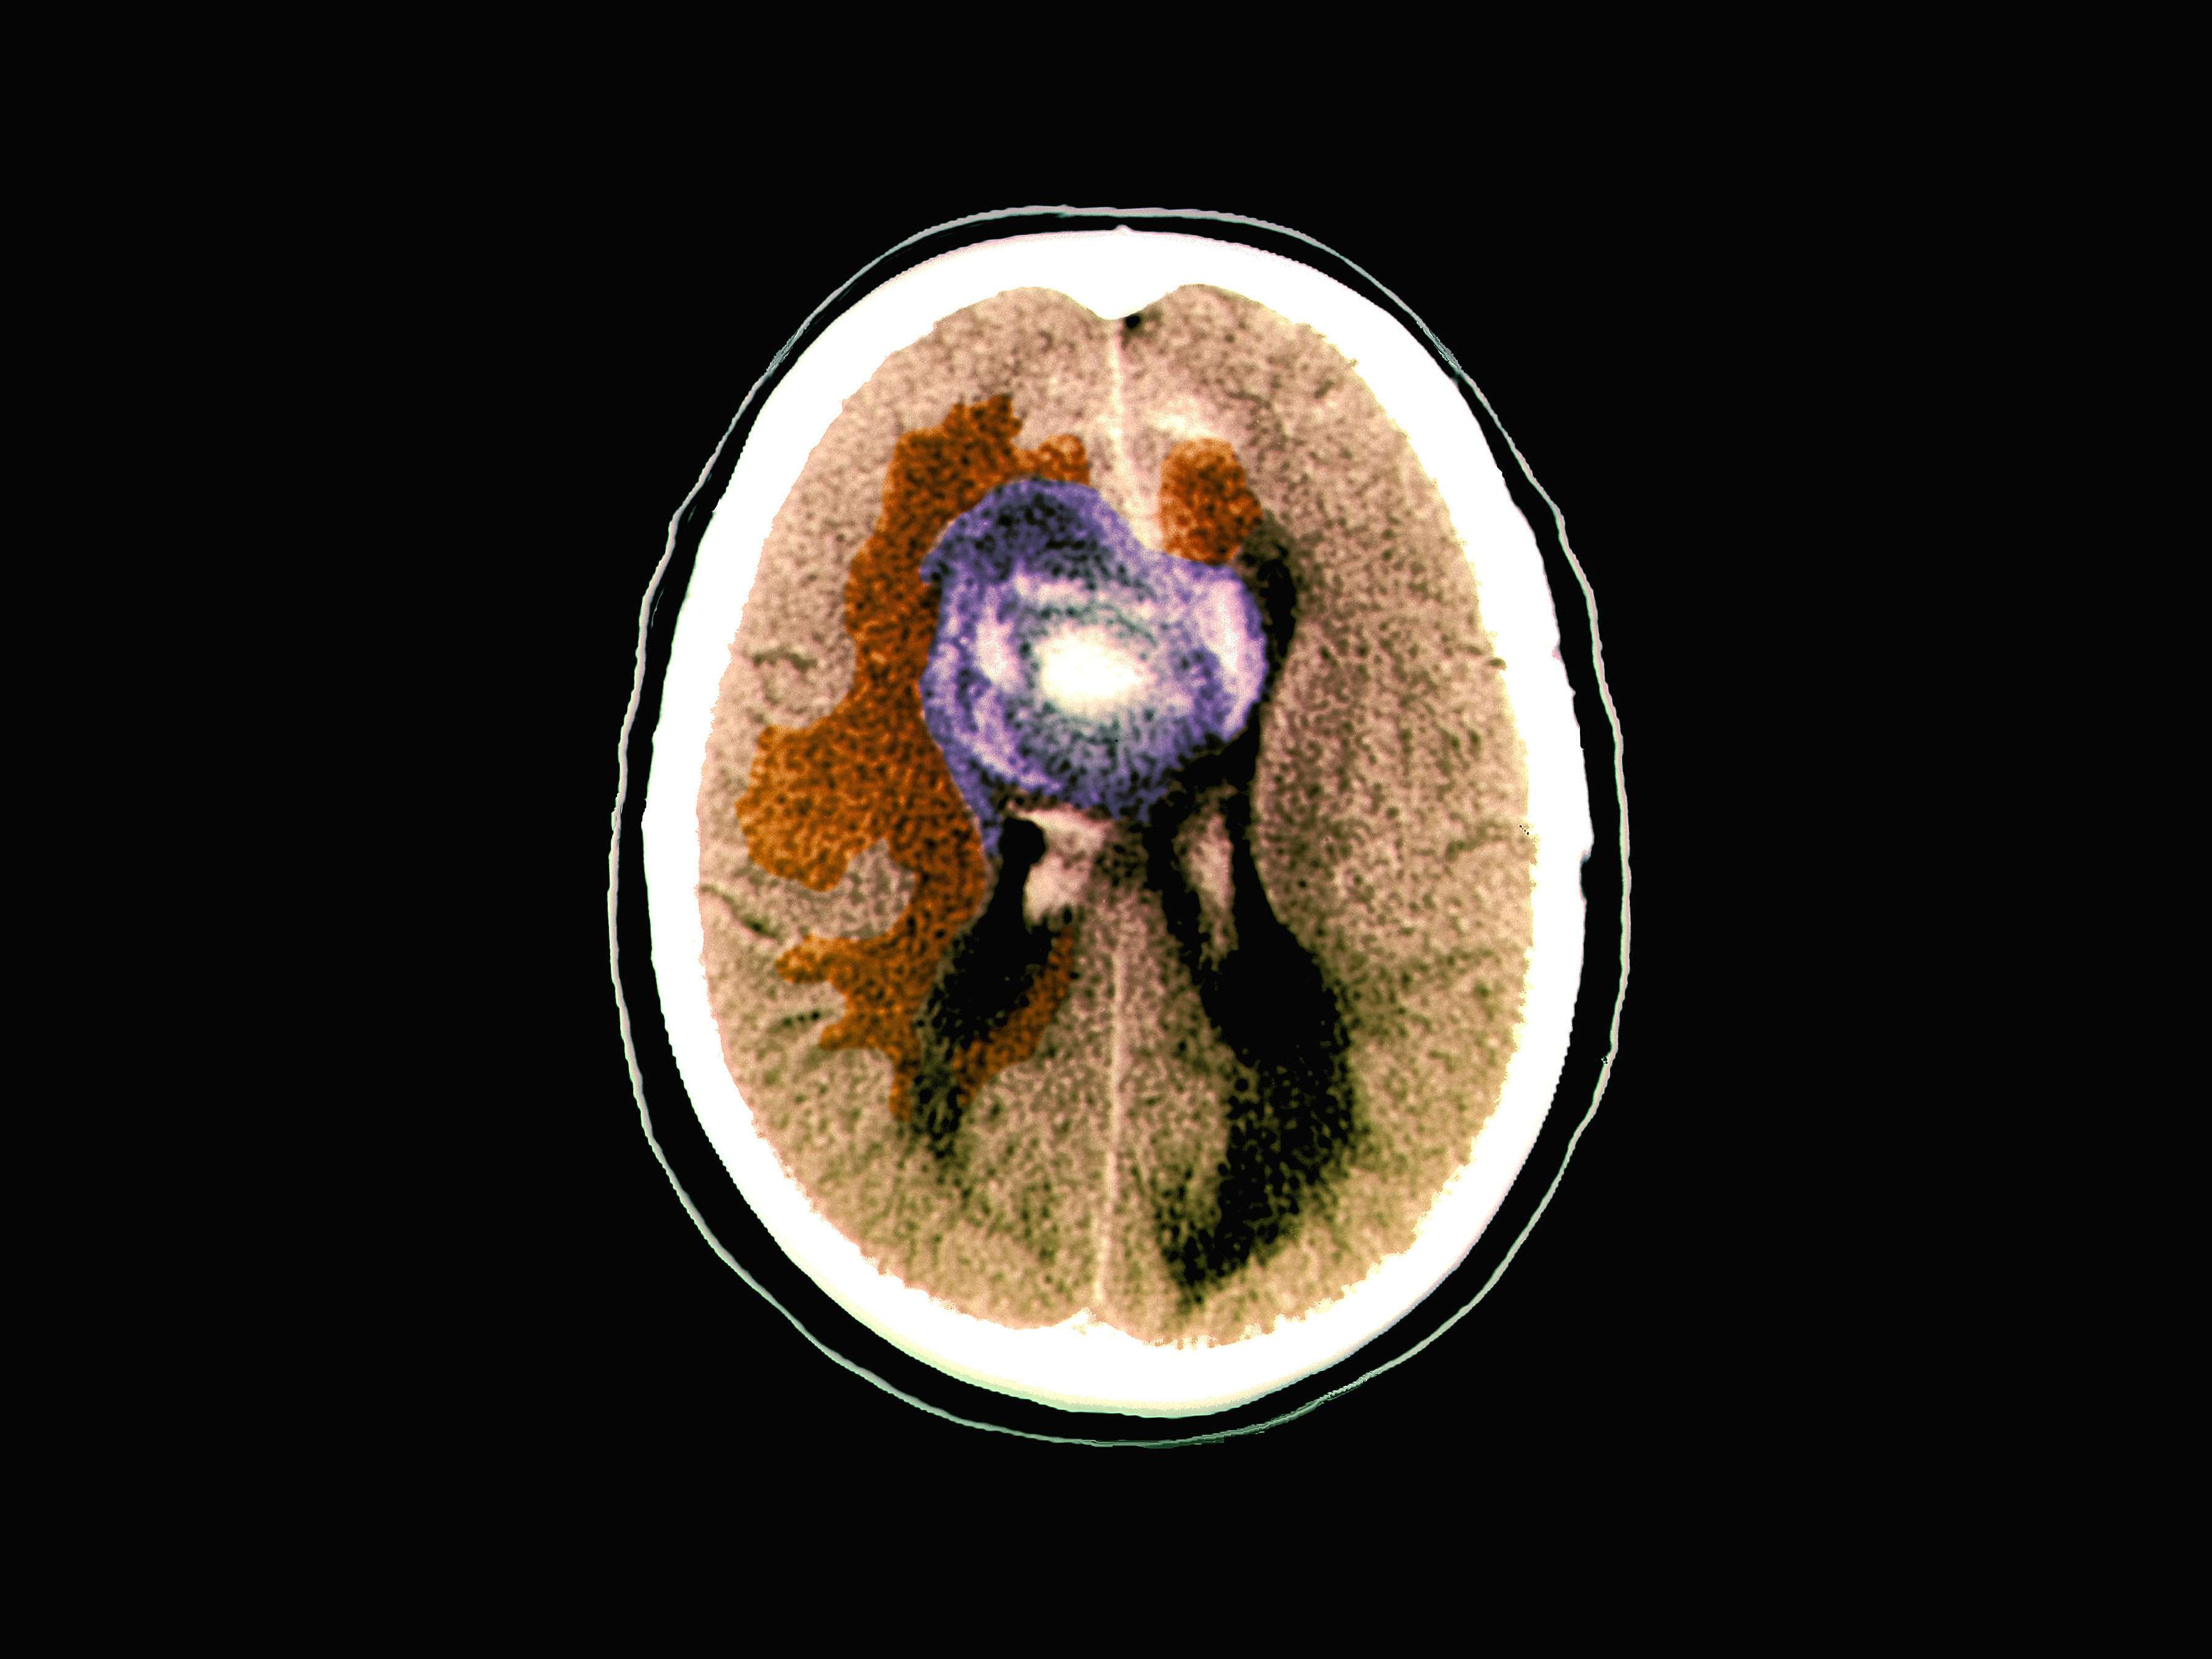

Deadly Brain Cancers Act Like 'Vampires' By Hijacking Normal Cells To Grow Researchers say certain brain cancers tap electrical signals from healthy cells to fuel their growth. The finding could lead to treatments for deadly tumors like the one that killed Sen. John McCain. Jon Hamilton